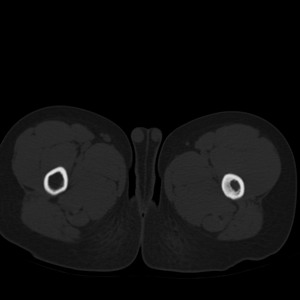

标题: PED1884:患者,男性,7岁。因右髋疼痛5天,而来院检查。 [打印本页]

标题: PED1884:患者,男性,7岁。因右髋疼痛5天,而来院检查。

因右髋疼痛5天,而来院检查。

我们考虑:1、骨皮质增厚症。2、畸形性骨炎。3、骨纤。

右髋疼痛,左侧病变,看来无症状。

支持左股骨上段骨纤维异常增殖症可能性大.